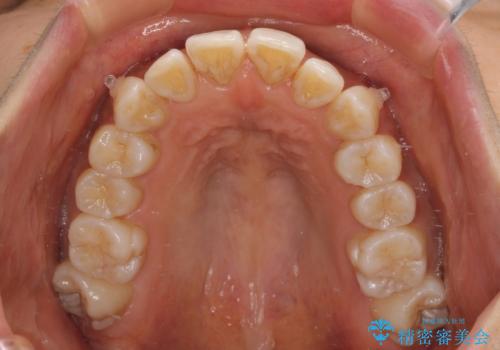

カリエールディスタライザーを併用したことで、確実かつ短期間で治療を終えることができました。